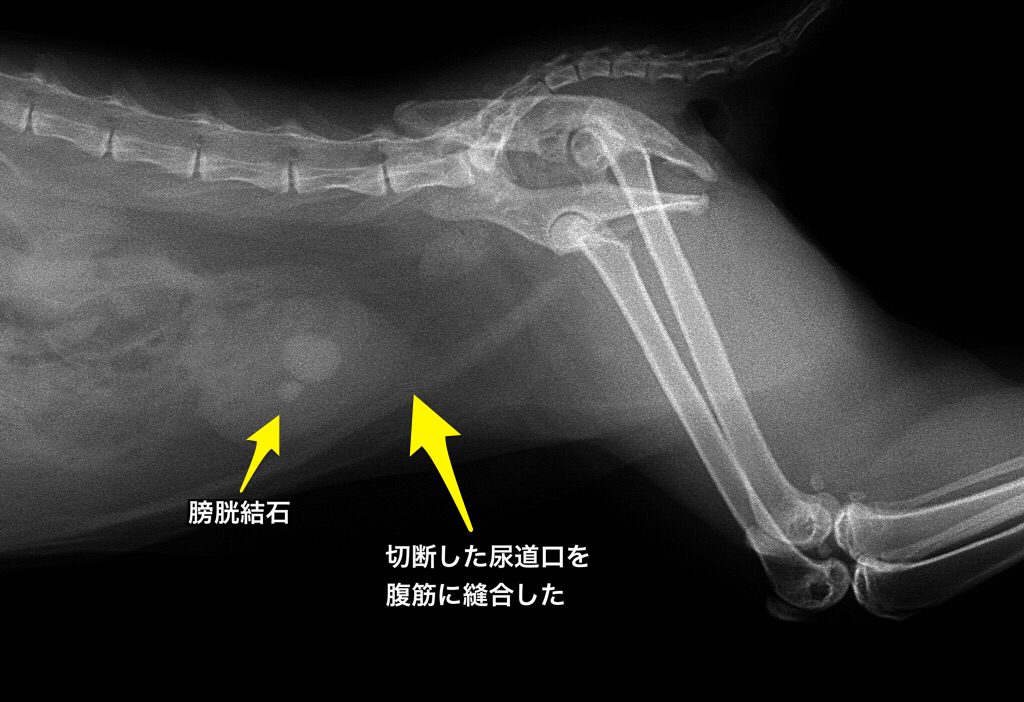

この子猫に関しては損傷のない尿道で切断し、その口をお腹の筋肉を切除して作った穴に縫い付けました。術後、写真などは撮っていませんでしたので、載せることはできませんが、その後、半年くらいして膀胱結石ができた時に撮ったレントゲン写真をお見せします。

上の写真で、下腹部にある丸い風船状のものが膀胱で、結石がその真ん中にあります。風船の口は普通、骨盤の方に繋がっていますが、お腹の壁に繋がっているのがわかると思います。下の写真がその穴にカテーテルの管を入れたところです。そこからおしっこが出ます。おしっこは普通に出すことは

できます。普通の猫ちゃんと変わらず、おしっこを溜めて尿意を催し、排尿します。